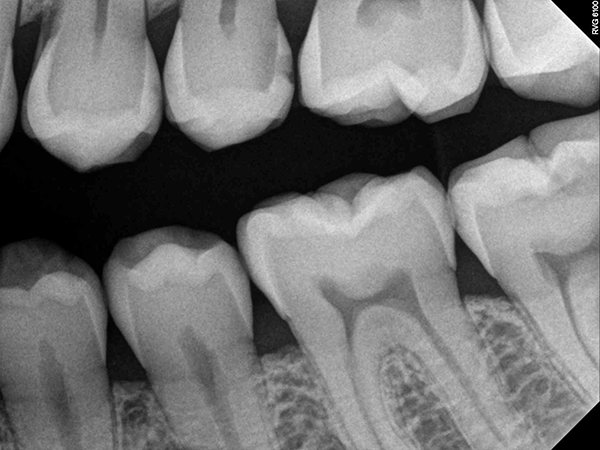

Visual examination revealed decay on the mesial marginal ridge and distal marginal ridge of tooth #13 as well as extensive buccal and occlusal decay on tooth #15 (Figs. 1-2). Bitewing radiographs and intraoral photographs were taken, which confirmed the above diagnosis and also exposed additional decay on the distal of tooth #12 (Figs. 3-4).

Fig. 3 Fig. 4